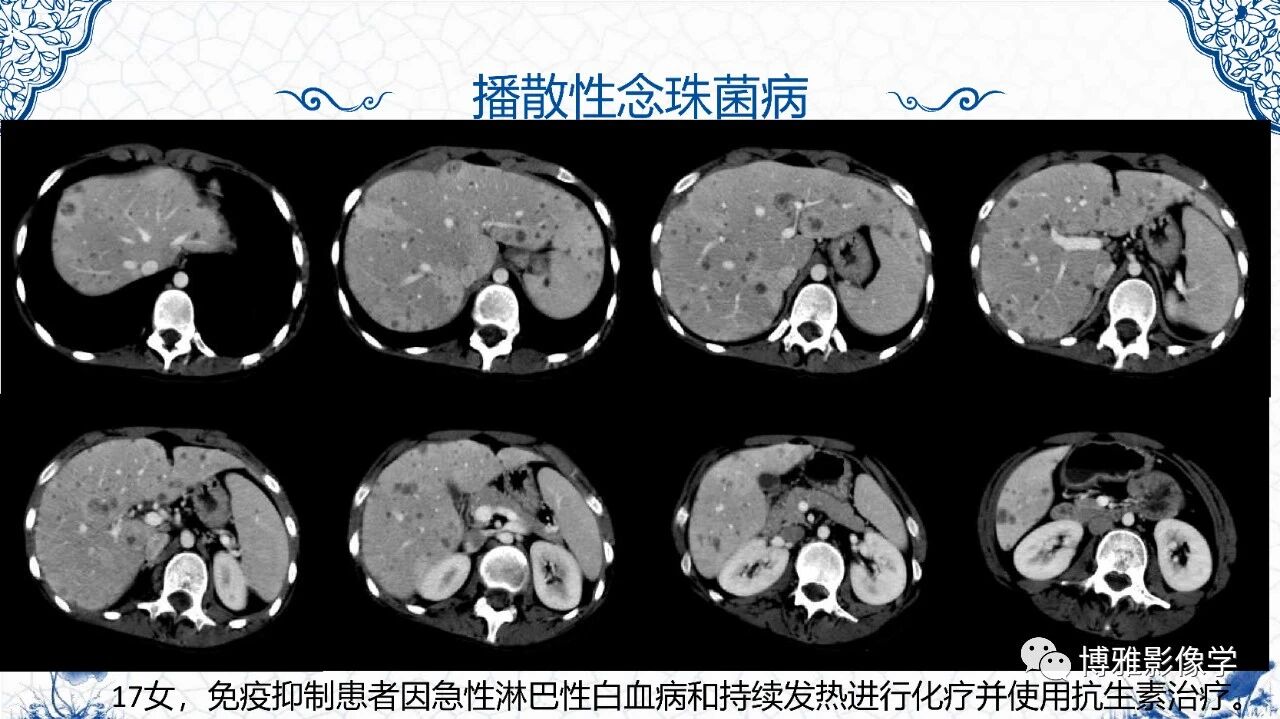

脾脏非肿瘤影像诊断